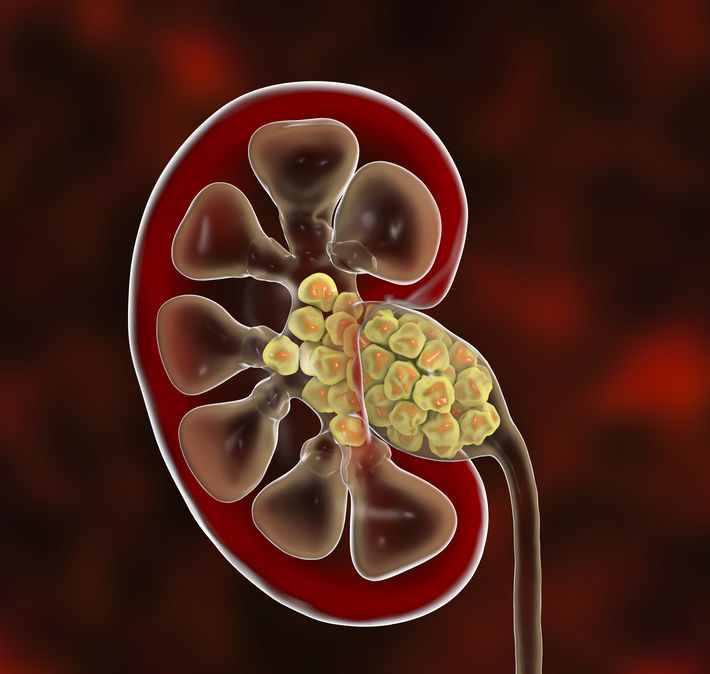

요로결석 원인으로 수분 섭취가 부족할 경우 발병하게 된다. 수분을 지나치게 적게 섭취할 경우 소변생성이 줄어들게 되고 요석 결정이 소변 속에 머무르는 시간이 길어지게 되면서 요석이 더욱 커져 요관을 막고 이로 인해 극심한통증을 유발하게 된다.

요로결석은 기온이 높은 여름철에 환자가 가장 많이 발생한다. 건강보험심사평가원 국민관심질병 2016년 통계에 따르면 요로결석증 환자는 기온이 높은 7월~9월에 진료인원이 가장 많았고, 8월에는 연중 최고치인 43,837명을 기록했다고 한다. 여름철에는 땀을 많이 흘리게 돼 체내 수분 손실이 크고, 햇빛에 많이 노출되는데 이때 체내의 비타민D가 많이 생성되어 이것이 장내의 칼슘 흡수를 촉진해 요로결석이 생기는 요인이 되기도 한다.

또다른 요로결석 원인으로 지리적으로 산이 많은 지역, 사막, 열대 지방에서 발생가능성이 높다. 환경적으로 수분 섭취가 낮을 수 있기 때문이다. 주로 40대가 가장 많이 발생하며 30대와 50대의 순서로 발병률이 높고, 여성에 비해 남성이 요로결석에 걸릴 확률이 2~3배가 높다.